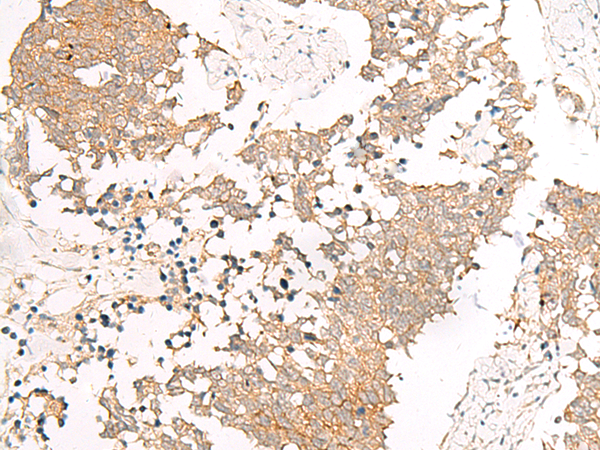

IHC positive control: |

Human tonsil and Human lung cancer |